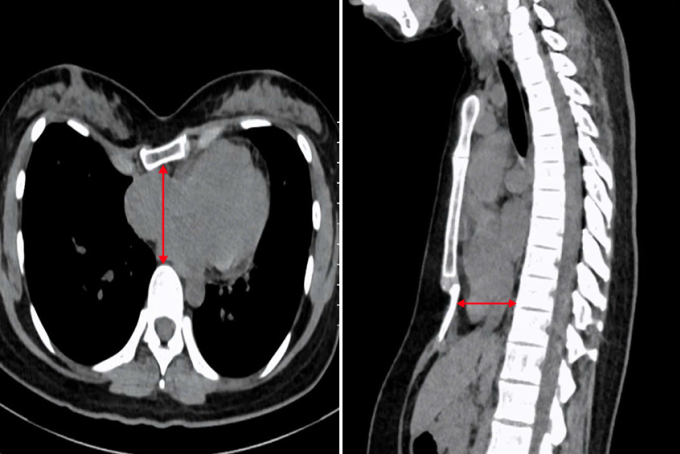

ThS.BS.CKI Phạm Ngọc Minh Thủy, khoa Ngoại Tim mạch, Trung tâm Tim mạch, Bệnh viện Đa khoa Tâm Anh TP HCM, cho biết chị Tây bị lõm ngực nặng, lệch về bên phải. Kết quả chụp cắt lớp vi tính ghi nhận chỉ số Haller là 5,2 (tỷ lệ giữa đường kính ngang và đường kính trước sau của ngực, bình thường chỉ số này dưới 2,5).

Chụp cắt lớp vi tính cho thấy ngực lõm nặng. Ảnh: Bệnh viện Đa khoa Tâm Anh